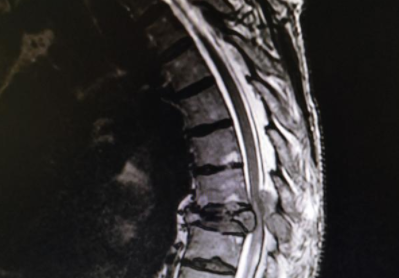

第一问:骨转移的高发部位在哪里?

一般来说,是脊柱和躯干的近段,脊柱包含颈椎、胸椎、腰椎和骶骨共24个椎骨,位于背侧躯干正中,而发生于脊柱的骨转移占比可以达到50%;另外比较常见的部位为股骨、肋骨和胸骨。

第三问:出现骨转移后,主要症状有哪些?

最常见的就是骨痛,其次可能出现病理性骨折,病理性骨折的表现和外伤等导致的骨折十分类似,有些患者表现为脊髓压迫的症状,比如类似腰椎间盘突出的表现、下肢的不适甚至大小便功能的障碍。还有就是可能在血生化检查中出现血钙增高等表现。